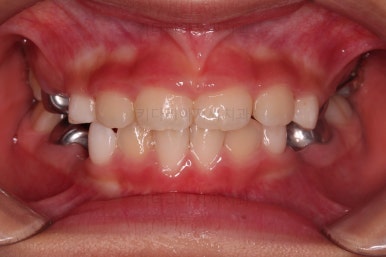

부산어린이반대교합 초진 시, 치열의 모습이에요.

우선 유치들이 많이 썩어서 치료가 필요해 보였고요.

앞니가 거꾸로 물려있고(아래 앞니가 위 앞니보다 앞으로 튀어나간 상황) 삐뚤어 있어요.